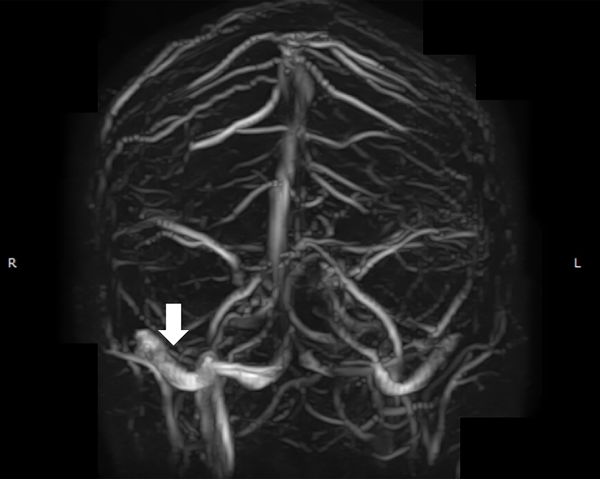

A la paciente se le había ofrecido cirugía de colocación de una válvula de derivación pero la misma rechazó esa opción. Se le realizó una angioRM con tiempos venosos que evidenció la presencia de estenosis de seno transverso derecho (figura 1) por lo que fue derivada a nuestro centro. Le realizamos una angiografía cerebral por punción radial derecha objetivando una estenosis del seno transverso derecho (figura 2A). A la vez, le realizamos un cateterismo venoso por punción femoral derecha y monitoreamos la presión a ambos lados de la estenosis del seno transverso (figura 2B). La presurometría evidenció un gradiente de presión entre el seno longitudinal superior y el seno sigmoideo derecho de 15mm de Hg (figura 2C) por lo que decidimos realizar la angioplastía del seno transverso a nivel de la estenosis.

Figura 1: Angioresonancia en tiempo venoso. La flecha blanca señala la estenosis del seno transverso derecho.